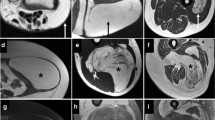

Differentiating atypical lipomatous tumors (ALTs) and well-differentiated liposarcomas (WDLs) from benign lipomatous lesions is important for guiding clinical management, though conventional visual analysis of these lesions is challenging due to overlap of imaging features. Radiomics-based approaches may serve as a promising alternative and/or supplementary diagnostic approach to conventional imaging.

A background review of the radiomic workflow is provided, outlining the steps of image acquisition, segmentation, feature extraction, and model development. Subsequently, a systematic review of MEDLINE, EMBASE, Scopus, the Cochrane Library, and the grey literature was performed from inception to June 2022 to identify size studies using radiomics for differentiating ALTs/WDLs from benign lipomas. Radiomic models were shown to outperform conventional analysis in all but one model with a sensitivity ranging from 68 to 100% and a specificity ranging from 84 to 100%. However, current approaches rely on user input and no studies used a fully automated method for segmentation, contributing to interobserver variability and decreasing time efficiency.

Radiomic models may show improved performance for differentiating ALTs/WDLs from benign lipomas compared to conventional analysis. However, considerable variability between radiomic approaches exists and future studies evaluating a standardized radiomic model with a multi-institutional study design and preferably fully automated segmentation software are needed before clinical application can be more broadly considered.